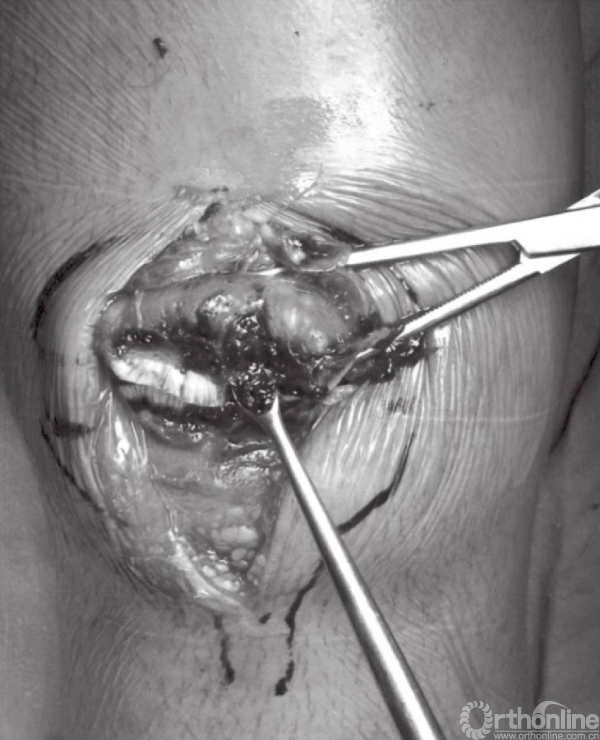

深层显露切口与皮肤切口方向一致。锐性分离深层筋膜,并牵开皮肤组织,进一步切开髌骨囊并清除血肿后骨折端即可显露(图4A和B)。此时,可见髌骨骨折以及撕裂的韧带。以生理盐水清洗血肿以及血凝块(图5)。撕裂的支持带可先辨识后,再进行修复。

图5 用刮勺清除骨折块中的血凝块,并以生理盐水冲洗关节

骨折末端应以小挂勺以及吸引器清除局部的血凝块。骨折端处的骨膜以及韧带应分离至骨折线周围2~3cm处,以免影响骨折复位。但应注意,不要清除髌骨周围过多的软组织,因为常有骨折块包含其中。